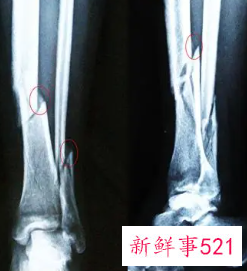

伤筋实际是韧带损伤、软组织损伤,骨头没有出现明显骨折;骨折是骨头裂了、碎了。患者先对受伤严重程度有个判断,依靠自身症状,比如脚踝崴了能不能走路作为判断,最准确的是到医院照X光片。严重者看不出来时可以照CT或者核磁共振以明确诊断,患者不能麻木大意。具体判断如下:

伤筋就是发生了肌肉、韧带以及肌腱的损伤,此时骨的连续性完好。而发生骨折时,患者会存在骨折端的错位、存在骨擦音,可以通过X线片的检查明确诊断。

所以患者发生外伤之后,需要积极地前往医院,进行拍片检查,排除是否存在骨折的情况,再给予有效治疗。如果患者发生了骨折,还需要根据骨折的严重程度,选择对应的治疗手段。

总而言之,病人自己首先对受伤的严重程度有个判断,此外,跟自身的症状,比如说脚踝崴了能不能走路来作为判断,最准的还是到医院照一张X光片。严重的话,看不出来的话,可以照一个CT或者核磁来明确诊断。

有时候这是不能够麻木的大意,在临床上看到很多人觉得摔了一跤没什么事,过两天一照片子,骨折了。